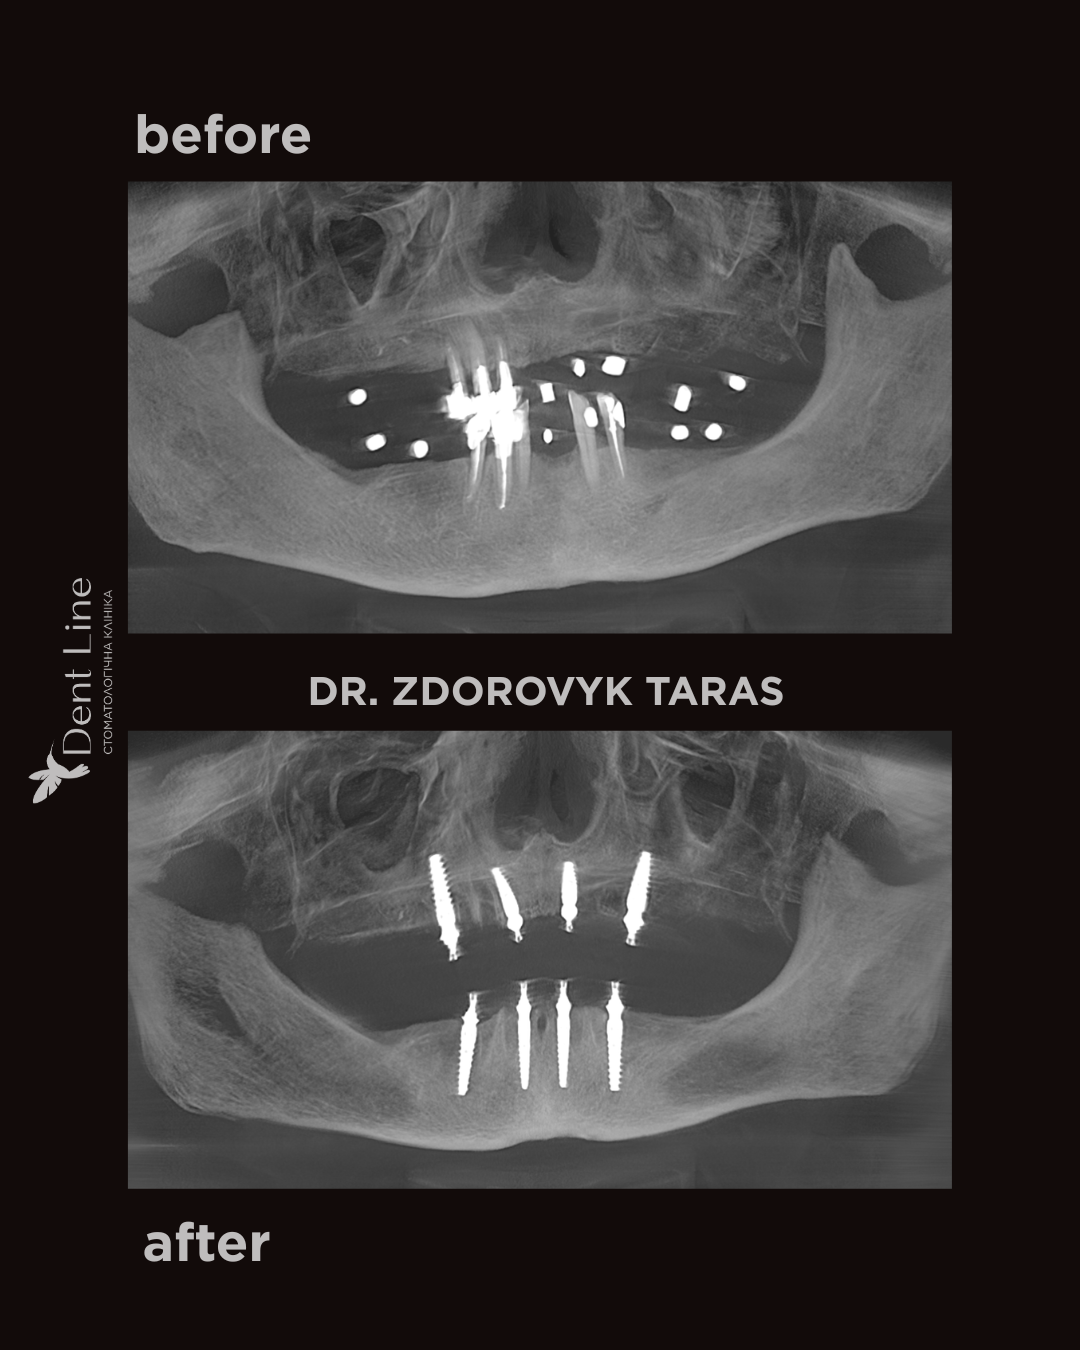

Пацієнтка звернулась до нас зі скаргами на втрату зубів внаслідок карієсу та його ускладнень, неможливість повноцінно пережовувати їжу та виражений естетичний дефект. Було проведено імплантацію за методикою All-on-4 — встановлення імплантів JDental на верхній та нижній щелепі з негайним навантаженням. Операцію виконано в один день. У день втручання пацієнтка отримала тимчасові ортопедичні конструкції, що дозволило одразу відновити естетику посмішки та функцію жування.

Після повного загоєння імплантів тимчасові конструкції будуть замінені на постійну ортопедичну роботу.